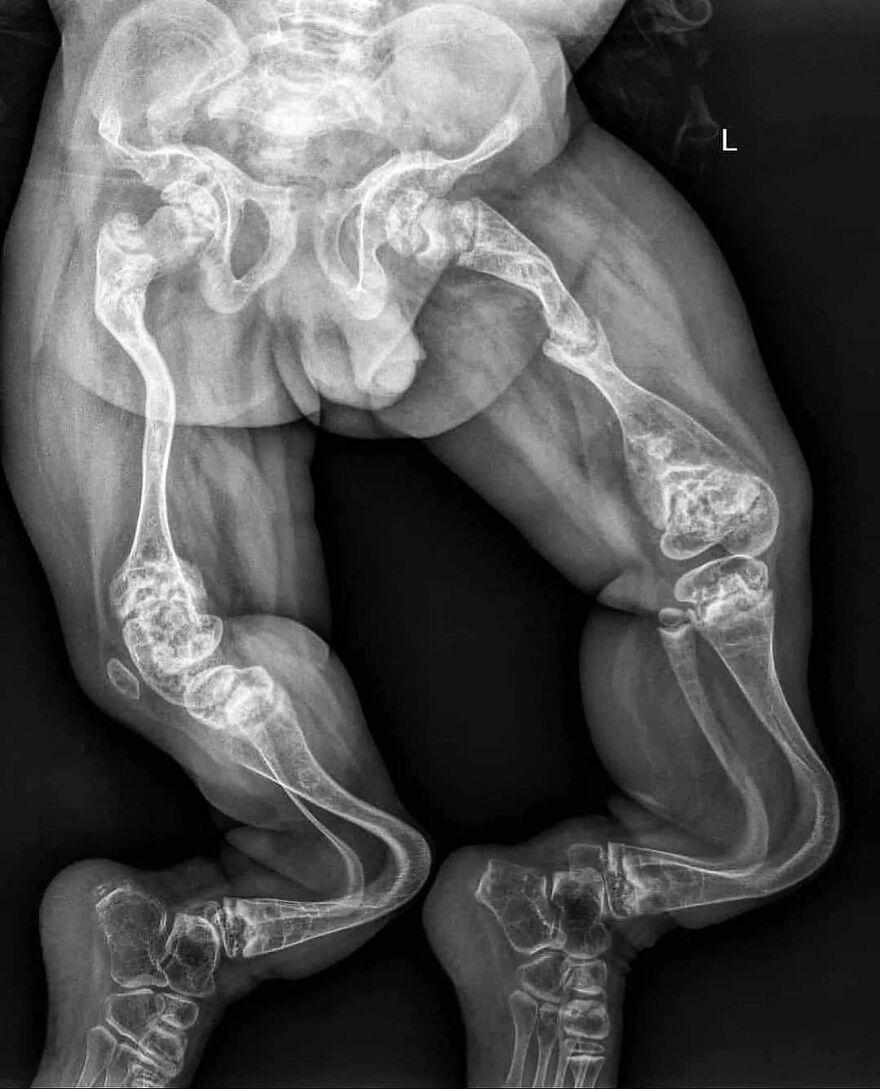

The entire human digestive system

HOLY MOTHER OF GODDESS GOD WHATEVER. I totally thought that was something else more horrifying